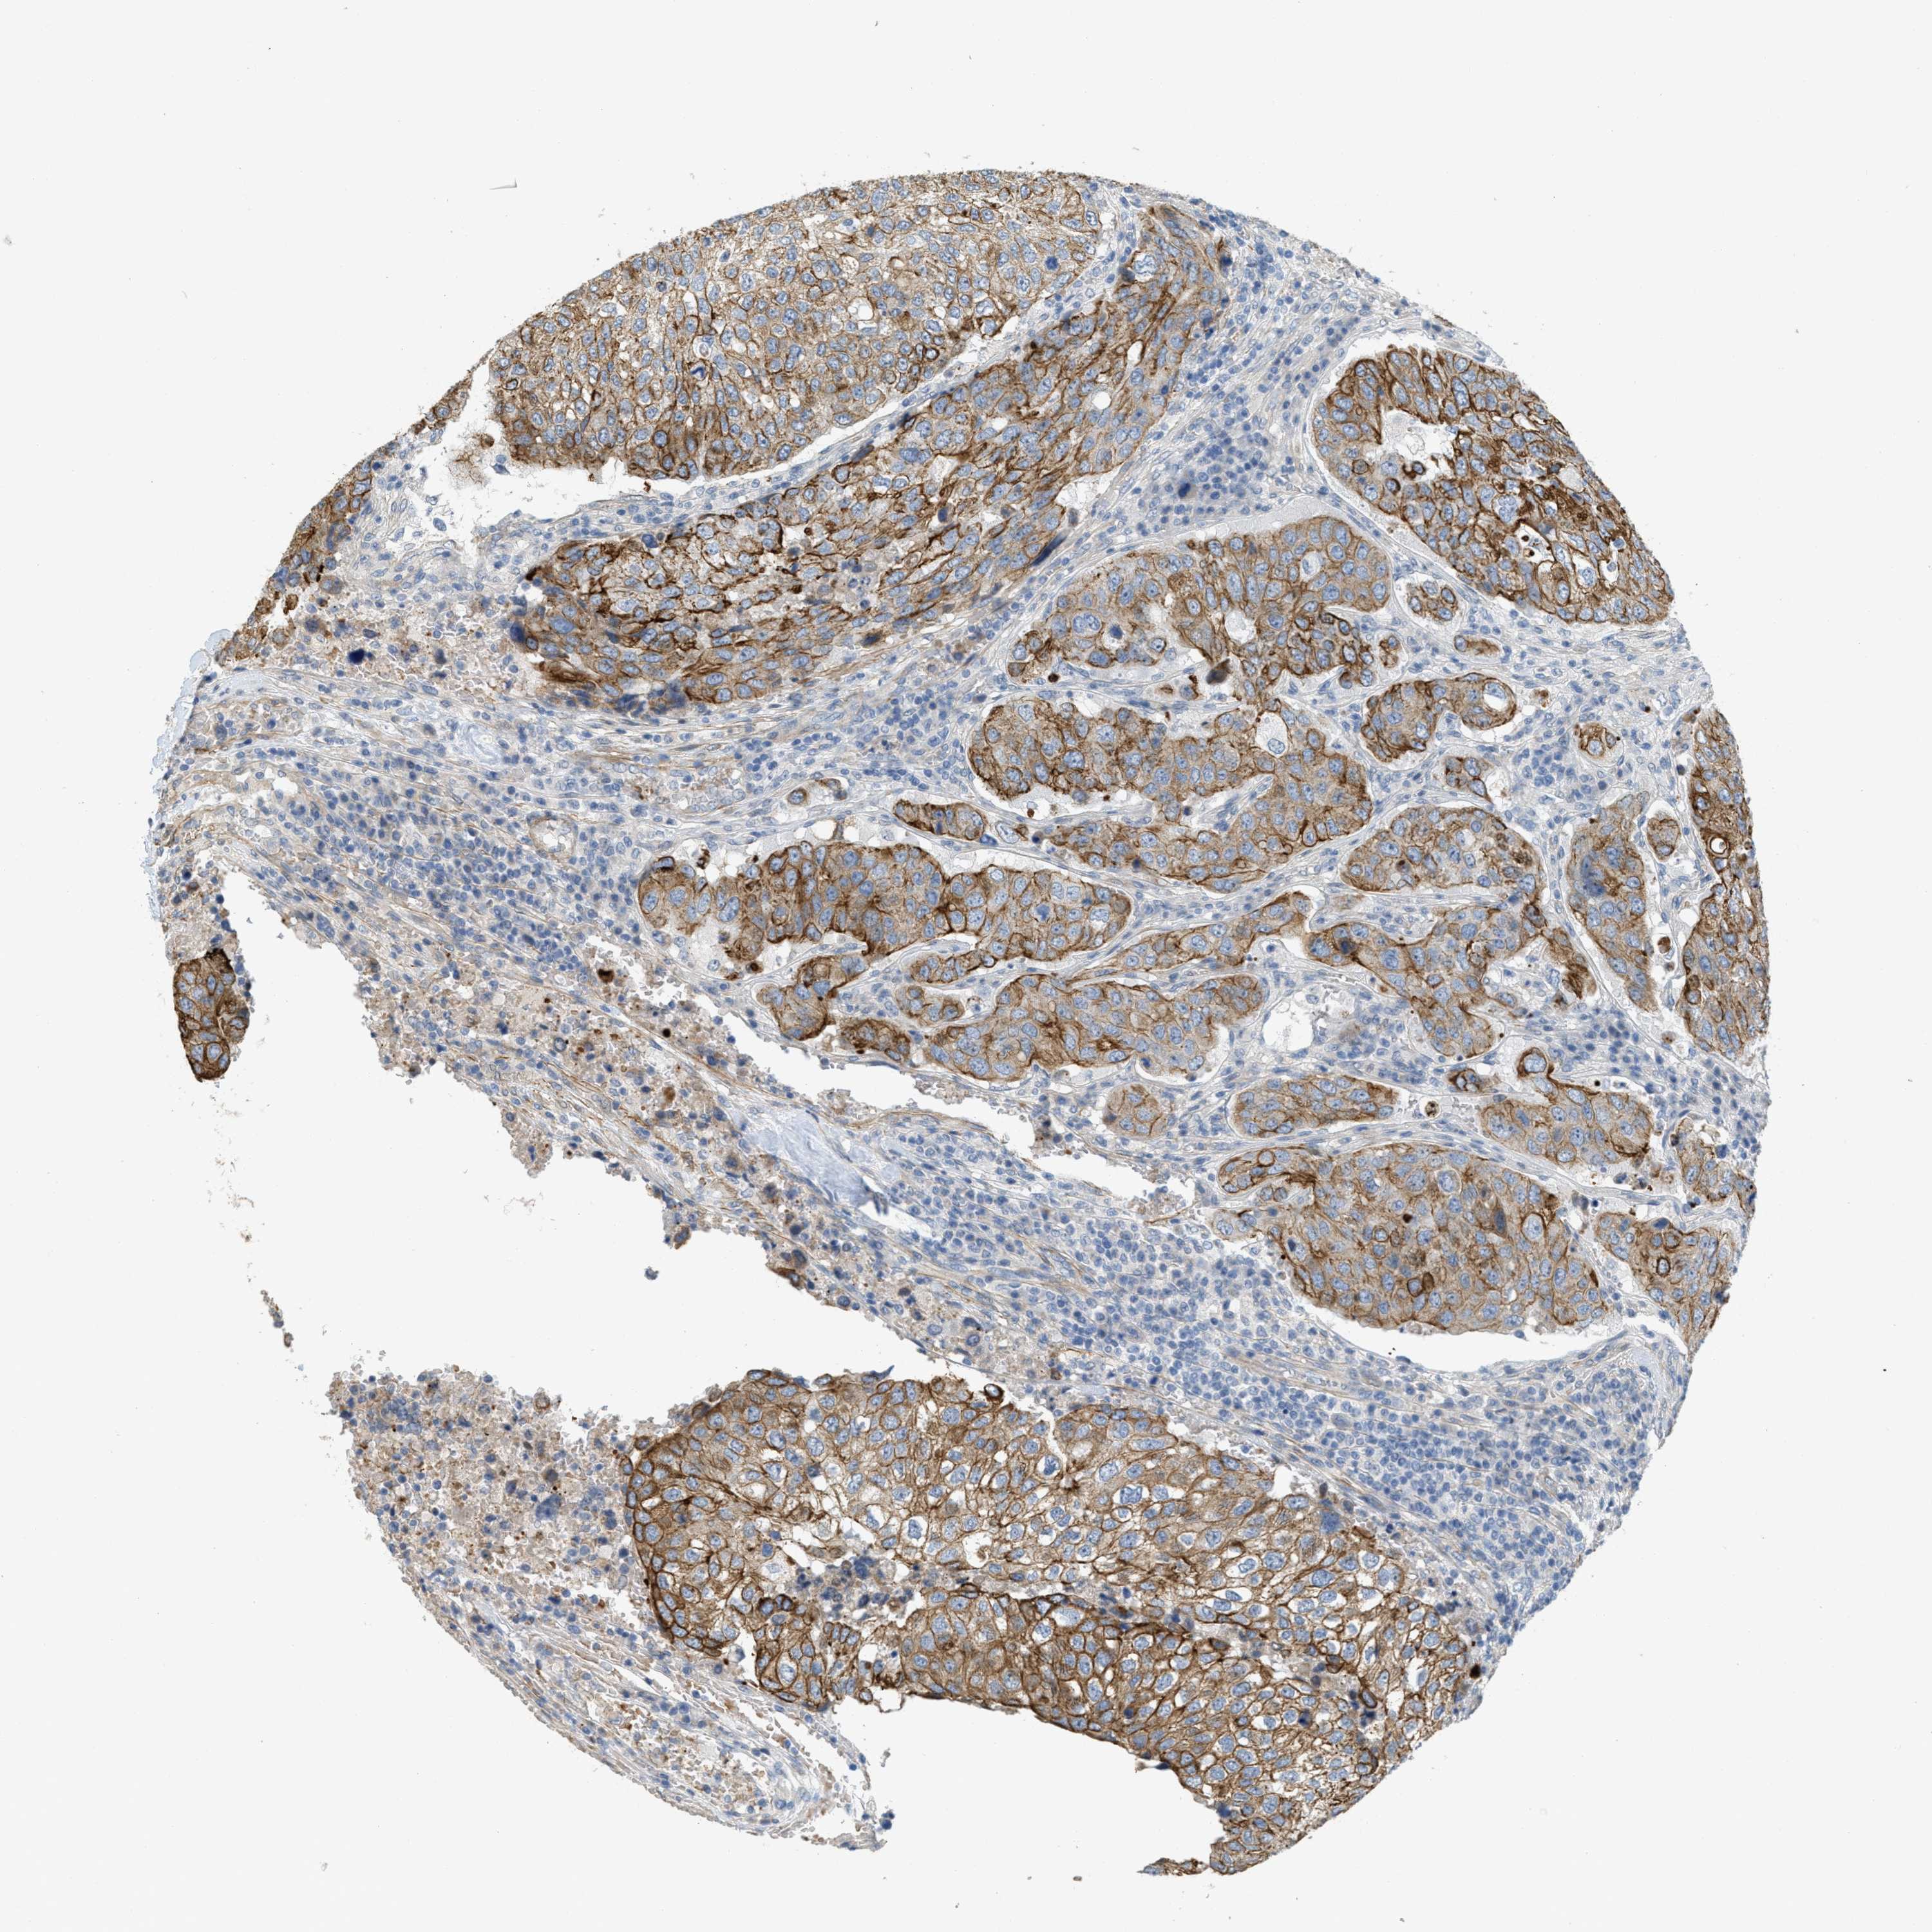

UROTHELIAL CANCER - Protein expressioni

A mouse-over function shows sample information and annotation data. Click on an image to view it in a full screen mode. Samples can be filtered based on level of antibody staining by selecting one or several of the following categories: high, medium, low and not detected. The assay and annotation is described here.

Note that samples used for immunohistochemistry by the Human Protein Atlas do not correspond to samples in the TCGA dataset.

Antibody stainingi

Antibody staining in the annotated cell types in the current human tissue is reported as not detected, low, medium, or high, based on conventional immunohistochemistry profiling in selected tissues. This score is based on the combination of the staining intensity and fraction of stained cells.

Each image is clickable and will lead to virtual microscopy that enables deeper exploration of all samples and also displays staining intensity scores, fraction scores and subcellular localization as well as patient and tissue information for each sample.

Antibody HPA017642

Staining

High

Medium

Low

Not detected

Intensity

Strong

Moderate

Weak

Negative

Quantity

>75%

75%-25%

<25%

None

Location

Nuclear

Cytoplasmic/membranous

Cytoplasmic/membranous,nuclear

Urothelial carcinoma, Low grade

Urothelial carcinoma, High grade